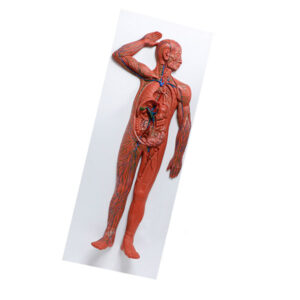

Modelo de sistema circulatório